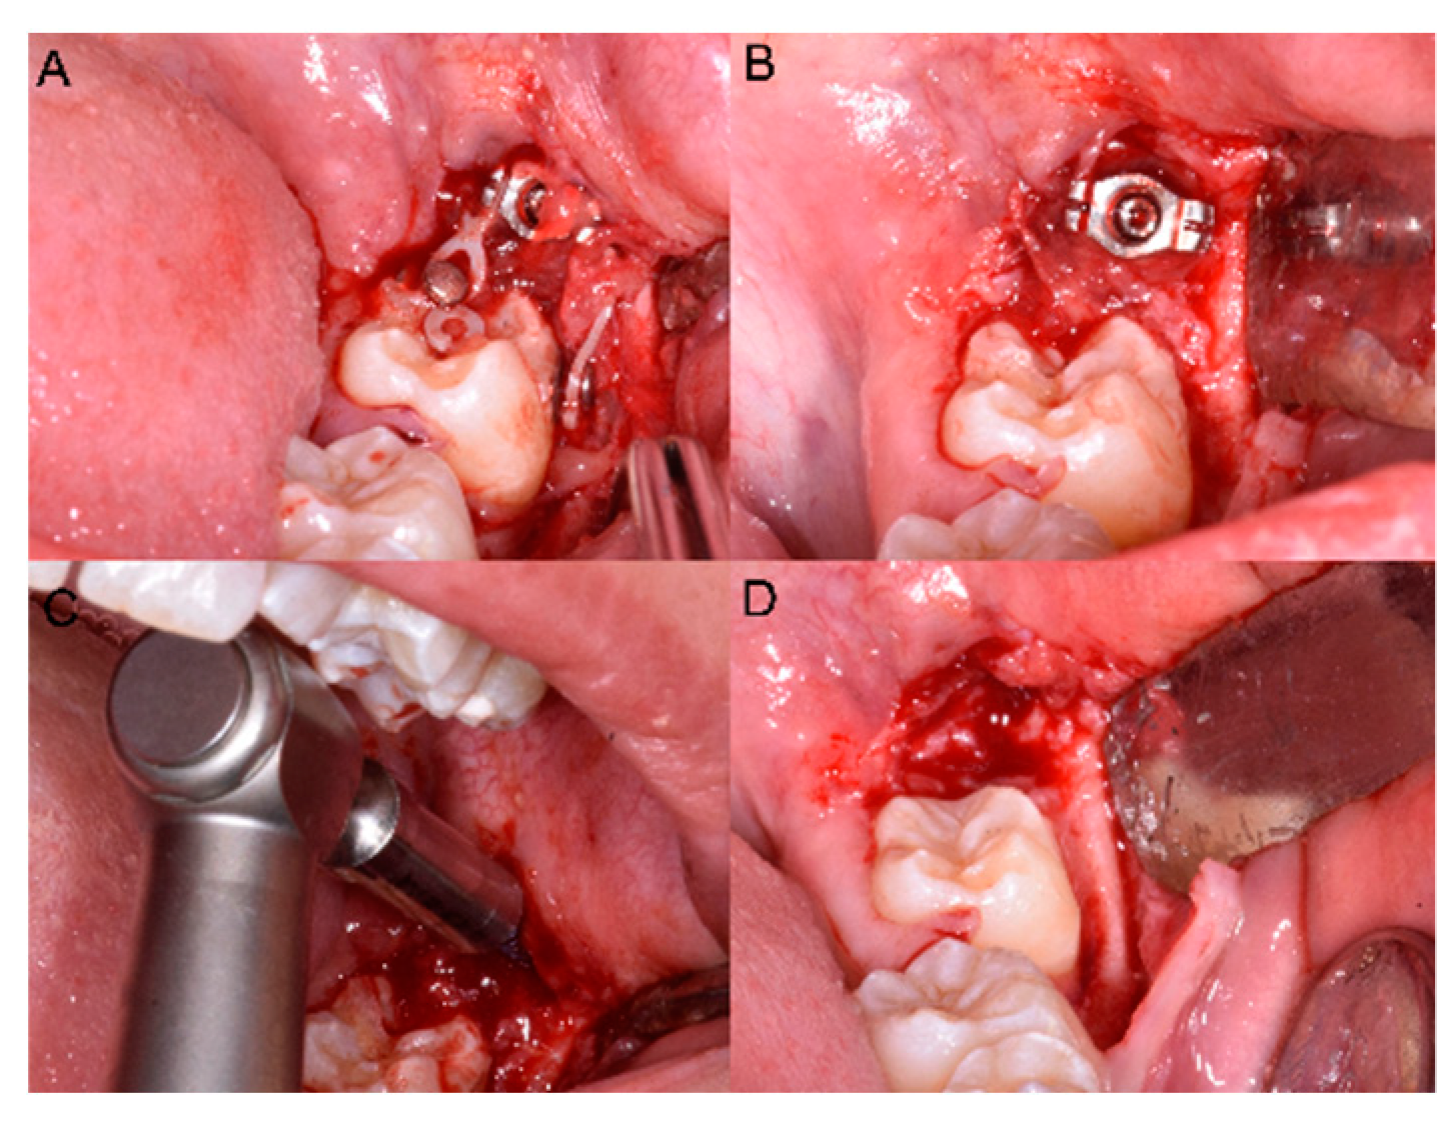

The panoramic radiograph showed the presence of several impacted teeth (Figure 1). Angle of inclination of MM2 was measured, as described by Evans [17]. The angle of the left MM2 was 30°, the angle of the right MM2 was 40°. Cephalometric measurements were performed using lateral cephalometric radiography that showed a Class I skeletal relationship (ANB = 2°), brachyfacial growth pattern (MP-SN = 30.5°; FMA = 17.5°) and palatal inclination of the upper incisors (U1—ANS-PNS = 107.0°).

Figure 1.

Pretreatment panoramic radiograph showing bilaterally impacted MM2 and upper canines.